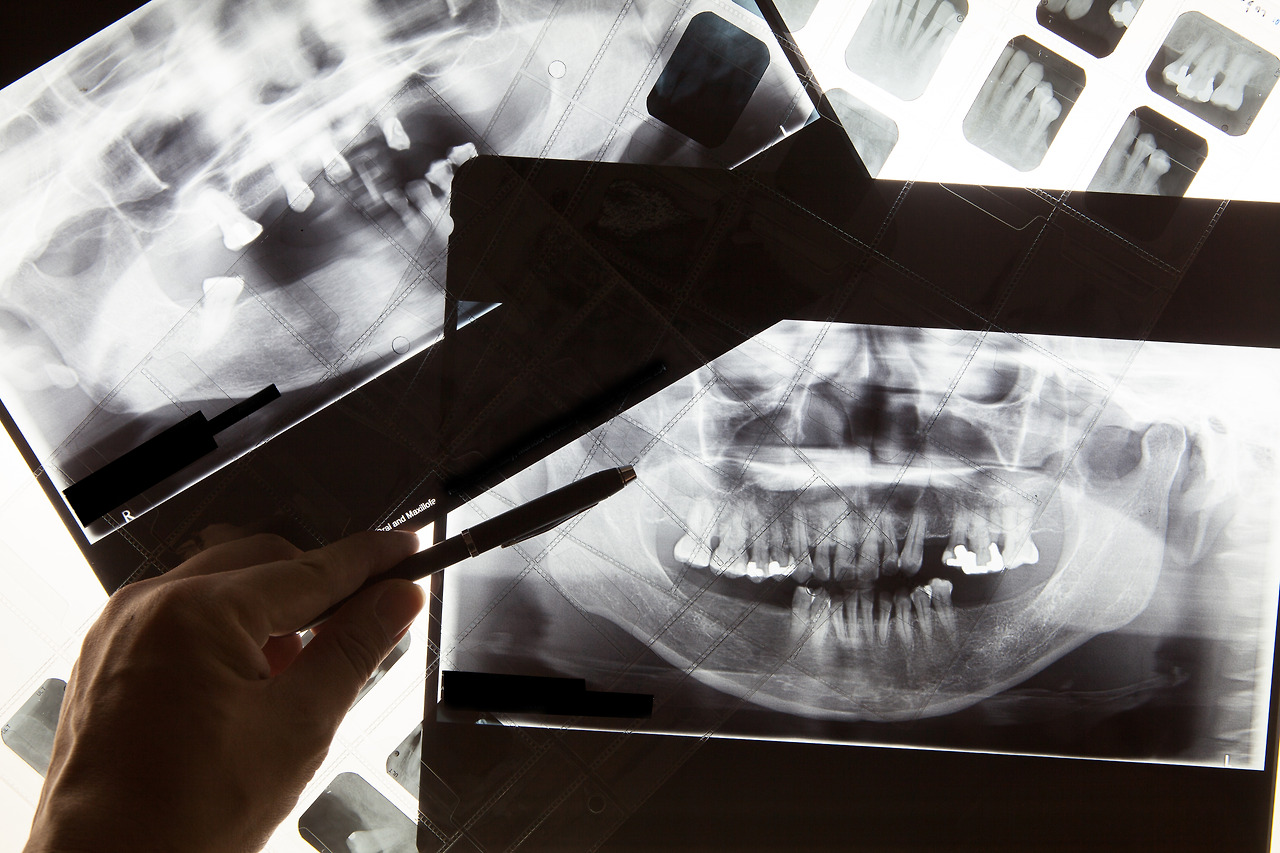

치아가 불편해 내원한 환자들 중 정확한 진단을 위해 치아 엑스레이를 찍자고 하면 '꼭 찍어야 하냐'라고 질문하시는 분들이 의외로 많습니다. 엑스레이에서 나오는 방사선이 염려되어 이를 불편하게 여기는 분들도 있고, 육안으로 치아 상태가 다 보이는데 굳이 찍어야 하나 의아해하는 분들도 있기 때문입니다.

하지만, 이것은 치아 엑스레이의 중요성을 오해해서 생기는 반응입니다. 우선, 치아 엑스레이 촬영 시 나오는 방사선의 양은 다른 과에 비하면 미비한 수준으로 크게 걱정할 정도는 아닙니다.

또한, 치아가 불편한 원인은 치아 뿌리나 신경 등 보이지 않는 치아 내부에서 기인한 경우가 많고, 치아에 미세하게 금이 간 경우는 육안으로 확인이 어렵기 때문에 이를 확인할 수 있는 치아 엑스레이는 필수적인 것이기도 합니다.

거기다, 교정이나 임플란트, 틀니 등 구강 및 안면구조를 정확하게 파악해야 하는 치료에도 치아 엑스레이는 반드시 필요한 진단 과정입니다. 특히, 변수가 많은 성장기 청소년들의 교정 치료에는 섬세하게 치아 상태를 관찰해야 하기 때문에 치아 엑스레이가 더욱 중요하게 활용됩니다.

이처럼 치아 엑스레이가 치과 치료 전반에 걸쳐 중요하게 평가받는 이유는 이를 통해 얻을 수 있는 정보가 많아 정확한 진단과 치료가 가능해진다는 것입니다.

가장 중요한 정보는 우리 눈으로 확인이 불가능한 치아 내부의 상황을 알 수 있다는 것이지요. 치아 뿌리의 염증이나 신경의 문제, 잇몸 내부에 숨어 있는 매복니 등은 물론 어린이들의 영구치가 다 존재하는지 알아보는 수단으로도 치아 엑스레이는 중요한 역할을 합니다. 또한, 잇몸 질환의 진행 여부, 치아에 금이 간 경우나 보철물의 상태 파악에도 유용하지요.

치아 엑스레이는 교정이나 임플란트, 치과적 수술이 필요한 경우 등에도 중요하게 활용됩니다. 이들 치료는 치아 상태는 물론 구강구조 및 안면 해부학적 구조까지 파악해야 하기 때문에 이를 정확히 보도록 돕는 치아 엑스레이는 중요할 수밖에 없는 것입니다.

치아 엑스레이는 종류도 여러 가지입니다.

그중 우리가 가장 많이 접하는 것이 파노라마인데요, 입체적인 구강 내부를 평면적으로 볼 수 있게 해 주는 엑스레이를 말합니다. 구강 내외부 상태와 치열 등을 한눈에 볼 수 있어 눈에 보이지 않는 질환이나 보철물 상태, 치아의 이상 여부 등을 파악할 수 있습니다.